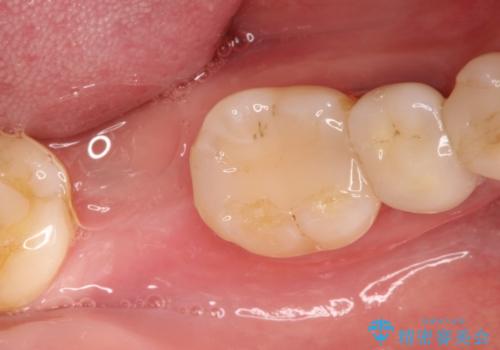

右下の奥歯を抜歯 インプラント治療による咬合回復

- 右下の奥歯をかぶせ物がとれたまま放置しているところに歯を入れたいとのことで来院されました。

精査すると保存が難しいため抜歯をして、インプラントを埋入、かぶせ物を装着する計画としました。

インプラント治療により、周りの歯を削ることなく咬合を回復することができました。